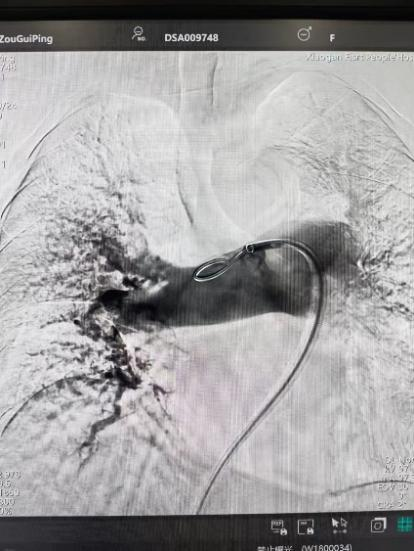

術(shù)前

手術(shù)在局部麻醉下進(jìn)行,團(tuán)隊(duì)通過(guò)股靜脈穿刺,將專用抽栓導(dǎo)管精準(zhǔn)送達(dá)肺動(dòng)脈栓塞部位,利用負(fù)壓抽吸技術(shù)成功清除大量血栓;隨后,在血栓局部精準(zhǔn)灌注溶栓藥物,進(jìn)一步溶解殘余血栓,恢復(fù)肺部血流灌注;同時(shí),為防止下肢深靜脈血栓再次脫落引發(fā)肺栓塞,團(tuán)隊(duì)為患者置入下腔靜脈濾器,整個(gè)手術(shù)歷時(shí)約1小時(shí)。術(shù)后,鄒婆婆呼吸困難癥狀即刻得到緩解,血氧飽和度顯著提升,右心負(fù)荷明顯減輕,目前身體狀況正在逐步恢復(fù)中。